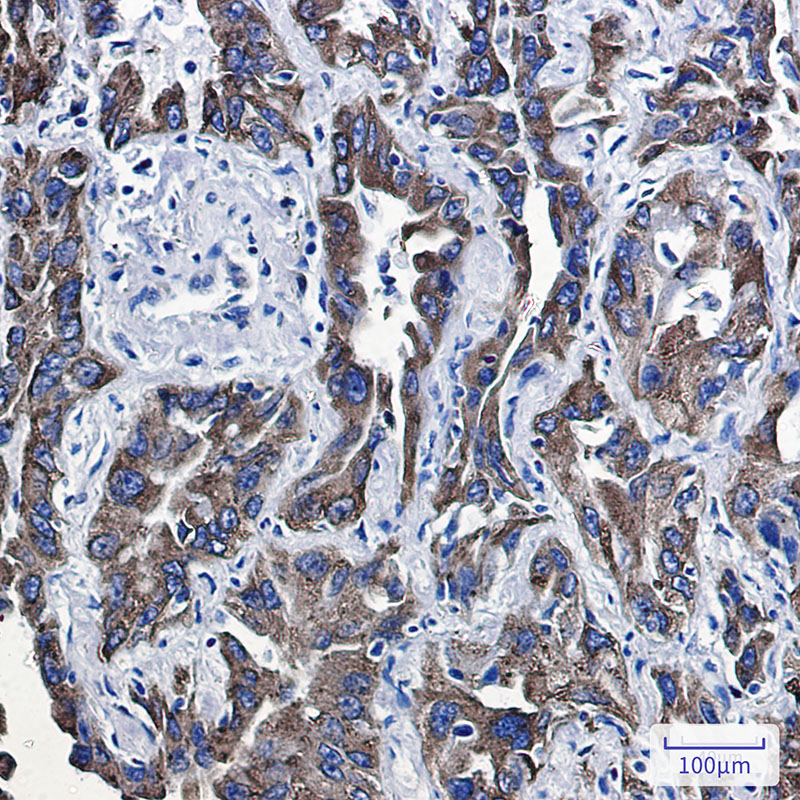

P4HB Rabbit mAb

| WB, IHC-P |

| Dilution | WB~~1:1000-1:5000 IHC-P~~1:50~200 |